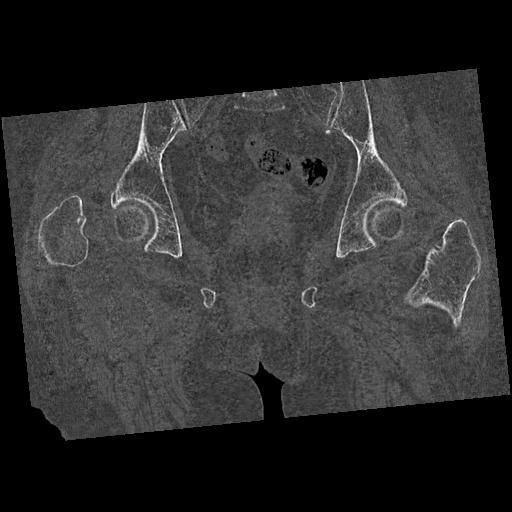

110286 2/17 股関節 2R 74歳女性 右人工骨頭

100703 1/27 両股正面+軸 1/29 両股正面+軸 94歳女性 パンソンロン

82084 1/14 1/20 股関節 2R 78歳男性 右人工骨頭

91569 3/25 両股正面とラウエン 70歳女性 人工骨頭+バンクーバー